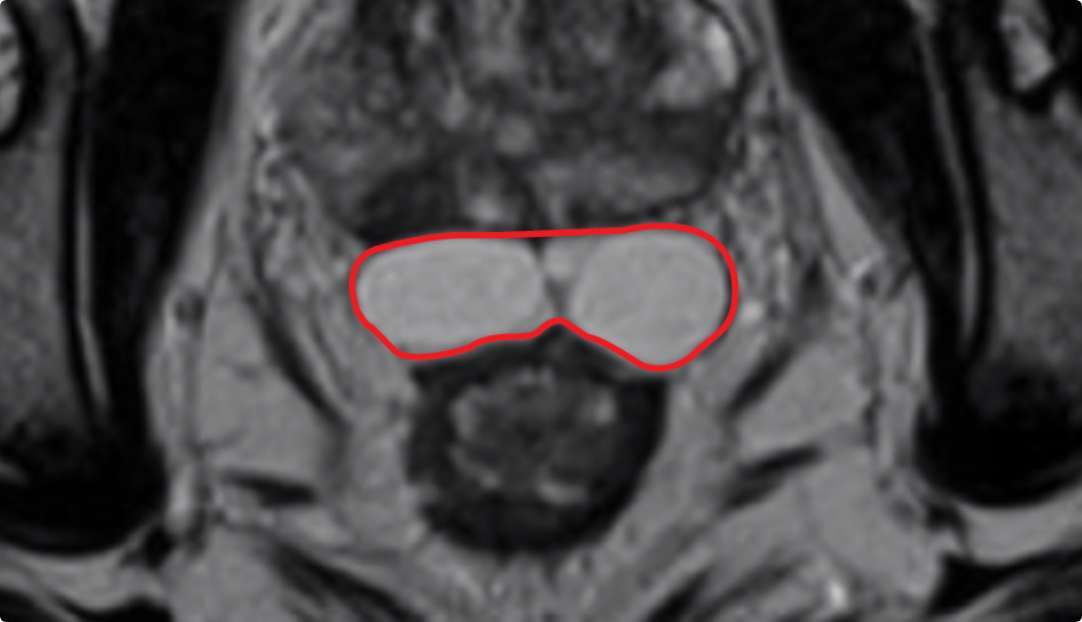

BARRIGEL

Implant Symmetry RESULTS6 >95%

Pivotal Trial Patients; % of implants centered on prostate midline

PEG HYDROGEL

Implant Symmetry RESULTS7 >49%

First Barrigel Cases - Consecutive Patients (Same Day)

TRUS images courtesy of Daniel R. Welchons, MD

Urologist; New York, United States